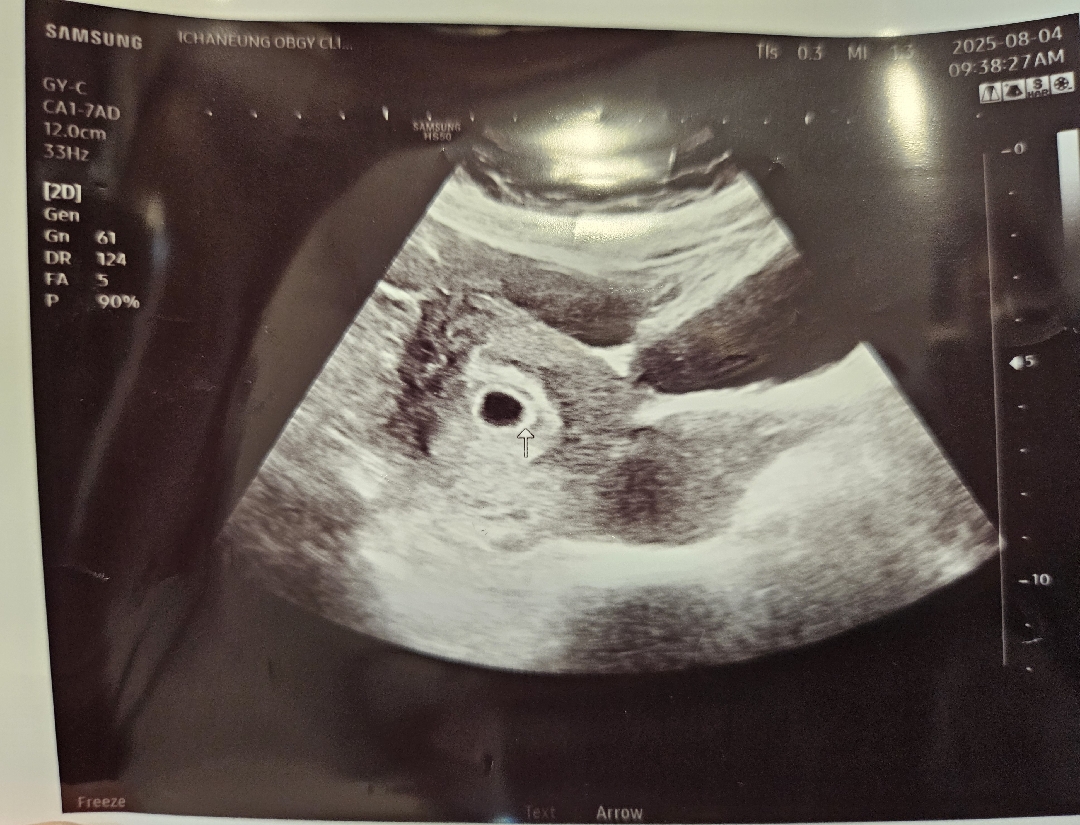

일주일 사이 집 더 크게 보수해놓구 사진찍으려니 벽에 딱 붙어서 숨어있네요ㅎㅎ 화살표에 애기 빼꼼❤️❤️ 2주뒤에 다시 초음파 보자고 하시네용 초음파 주수로는 5주~ 생리 주기로는 6주3일!